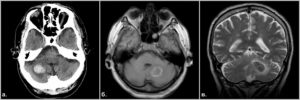

Острые нарушения кровообращения в мозжечке составляют инфаркты (некроз) либо кровоизлияния, которые имеют схожие механизмы развития с другими формами внутримозговых инсультов, поэтому факторы риска и основные причины будут совпадать. Патология встречается у людей среднего и пожилого возраста, чаще обнаруживается среди мужчин.

На долю инфаркта мозжечка приходится около 1,5% всех внутримозговых некрозов, в то время как кровоизлияния составляют десятую часть всех гематом. Среди инсультов именно мозжечковой локализации примерно ¾ приходится на инфаркты. Смертность высока и в иных случаях превышает 30%.